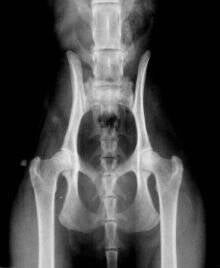

• HD (Heupdysplasie)

Het is een afwijking van het heupgewricht. De heupkom kan te ondiep zijn om de heupkop goed te kunnen ondersteunen, waardoor de heupkop niet goed past. Dit kan resulteren in het onherstelbaar degenereren van het kraakbeen. Wanneer er geen kraakbeen meer is, zullen de botten elkaar raken bij het bewegen. Dit is erg pijnlijk voor een kat en kan leiden tot manken, stijf lopen of moeilijk springen. Bij ernstige heupdysplasie is een operatie soms onvermijdelijk om de kwaliteit van het leven te verbeteren.

Een kat met normale heupen:

Een kat met HD graad 3;